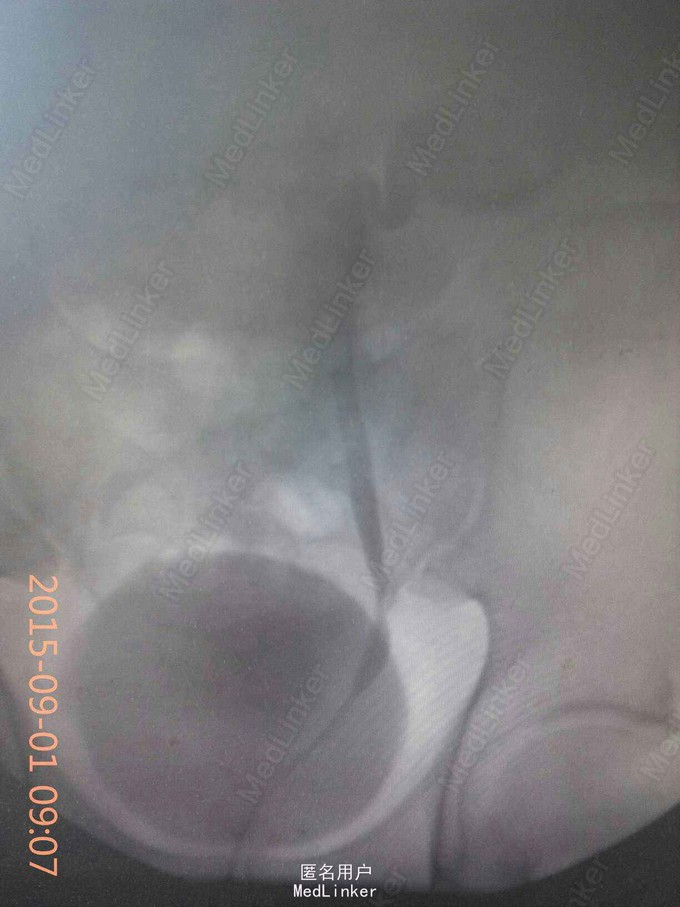

双肾区叩痛阴性,泌尿系CT左输尿管占位,逆行泌尿系照影左输尿管中段狭窄,狭窄以上未显影,输尿管镜取病理,回报输尿管息肉(组织小)

左输尿管占位,行输尿管占位切除,端端吻合术